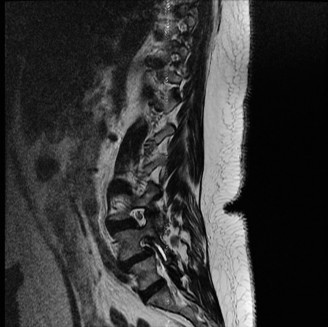

To contextualize the decision-making algorithm, consider the classic presentation of a middle-aged patient with multiple medical comorbidities. A paradigmatic case involves a 48-year-old obese female (Body Mass Index of 43) with poorly controlled diabetes mellitus who presents with severe, unrelenting low back pain, fevers, and chills. Advanced imaging, specifically magnetic resonance imaging (MRI), typically demonstrates discitis involving the L4–5 disc space with adjacent osteomyelitis of the L4 and L5 vertebral bodies. Crucially, in many early or medically responsive cases, there is an absence of epidural abscess formation, and standing radiographs reveal relatively normal sagittal and coronal alignment. When such a patient is neurologically intact—lacking saddle anesthesia, bowel/bladder incontinence, or upper motor neuron signs—the immediate clinical imperative shifts from urgent surgical decompression to aggressive pathogen identification and targeted antimicrobial therapy.

Pre-Operative Planning, Templating, and Patient Positioning

When surgical intervention becomes unavoidable, meticulous pre-operative planning is the cornerstone of a successful outcome. Advanced imaging is non-negotiable. An MRI with and without gadolinium contrast is the gold standard for defining the extent of the epidural abscess, the degree of neural compression, and the involvement of adjacent paraspinal musculature (e.g., psoas abscess). T1-weighted images typically show hypointense signals in the infected marrow, while T2-weighted and STIR sequences reveal hyperintense fluid and edema in the disc space and vertebral bodies. Gadolinium enhancement highlights the vascularized inflammatory phlegmon and the capsule of any abscesses.

In addition to MRI, a fine-cut computed tomography (CT) scan is essential for evaluating bony destruction. CT allows the surgeon to assess bone stock for pedicle screw purchase and to template the size of the interbody cages required for anterior column reconstruction. Upright standing radiographs (if the patient can tolerate them) or full-length supine films are necessary to evaluate global spinal alignment and regional kyphosis.